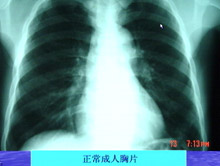

主持人:王丽(护士)是什么时候感染的? 王丽:我自己也不能明确说出自己的感染潜伏期有多长,但是我有明确的非典病人接触史,因为我在重症病房工作,3月13日我刚下班就发现自己双腿比较软,人有一种往下坠的感觉,开始以为是太疲劳导致的,回到宿舍量体温发现体温是38.4度,这时我赶紧就给科室打电话,然后拍了一个胸片后最终确诊为非典型肺炎。 张敏州:钟医生是我院第一个明确感染非典型肺炎的病人,最开始并不知道是感染了非典型肺炎,和黄丽护士一样开始都有疲乏无力的症状。 林琳:来看看胸片的情况:黄发胜的胸片可以看到一大片的阴影,发生了实变,正常的肺泡是充满空气的,而现在黄发胜的胸片显示没有空气。钟医生的胸片可以看到肺叶有发炎的现象。非典型肺炎的发病与季节有很大的关系,春天是呼吸系统疾病的高发季节。